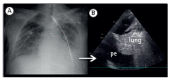

Lung ultrasound in the evaluation of pleural effusion